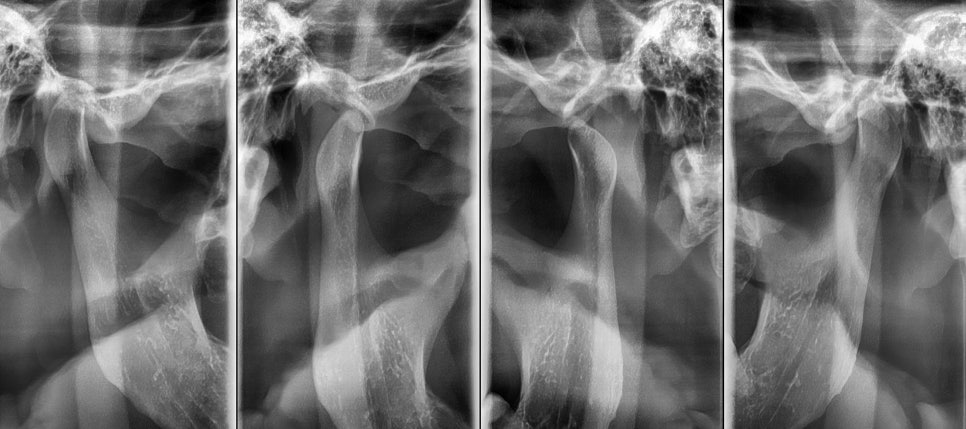

먼저 정밀한 진단과 분석을 통해

골격적 문제와 치아 배열 문제를

구분하여 평가합니다.

23.09.01

3차원 영상 분석과 모델 분석을 통해

치료 계획을 수립하게 되어요.